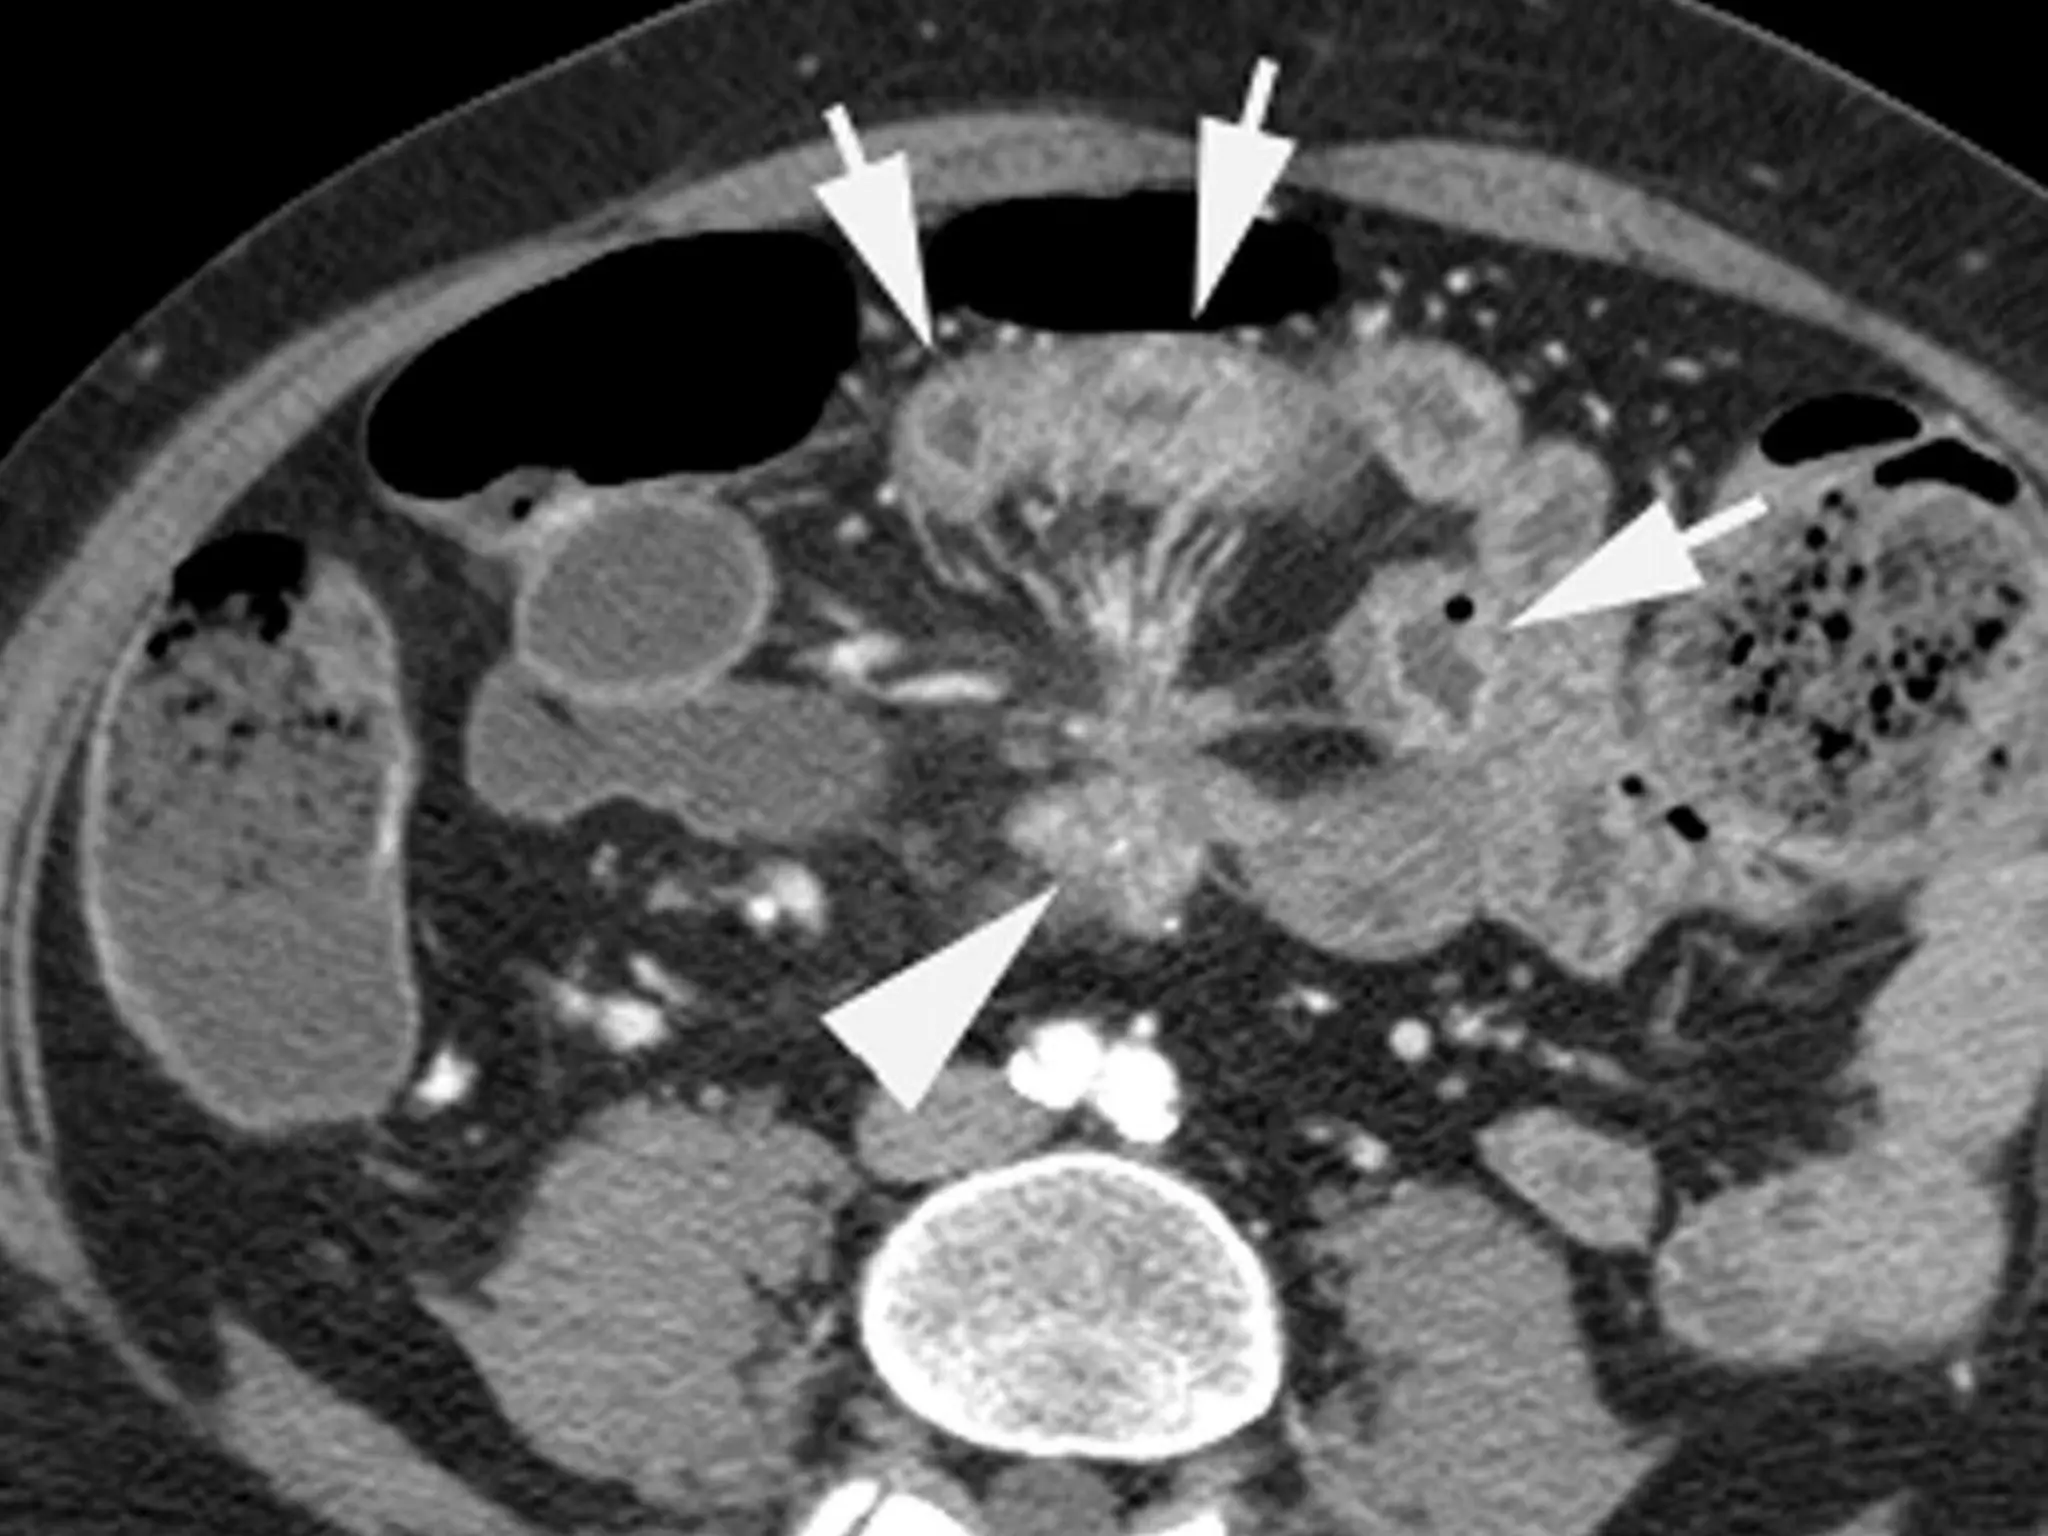

• #11 hypervascular enhanced intraluminal mass

• #12 Figure 15d.  Varied appearances of small bowel carcinoid tumors. (a) CT enterogram demonstrates a submucosal carcinoid tumor (arrows) within a Meckel diverticulum. (b) CT enterogram obtained in a different patient demonstrates a carcinoid tumor (arrow) within the wall of the ileum. (c) CT enterogram obtained in a third patient shows mesenteric metastases from an ileal carcinoid tumor. Note the enhancing, star-shaped mesenteric nodule (arrowhead), with stranding of the mesentery and thickening of the adjacent small bowel wall (arrows). The segmental wall thickening may indicate either a carcinoid carpet lesion or segmental edema. (d) Coronal reformatted CT enterographic image obtained in a fourth patient demonstrates a mesenteric carcinoid tumor (arrows) with hypervascular liver metastases (arrowheads).